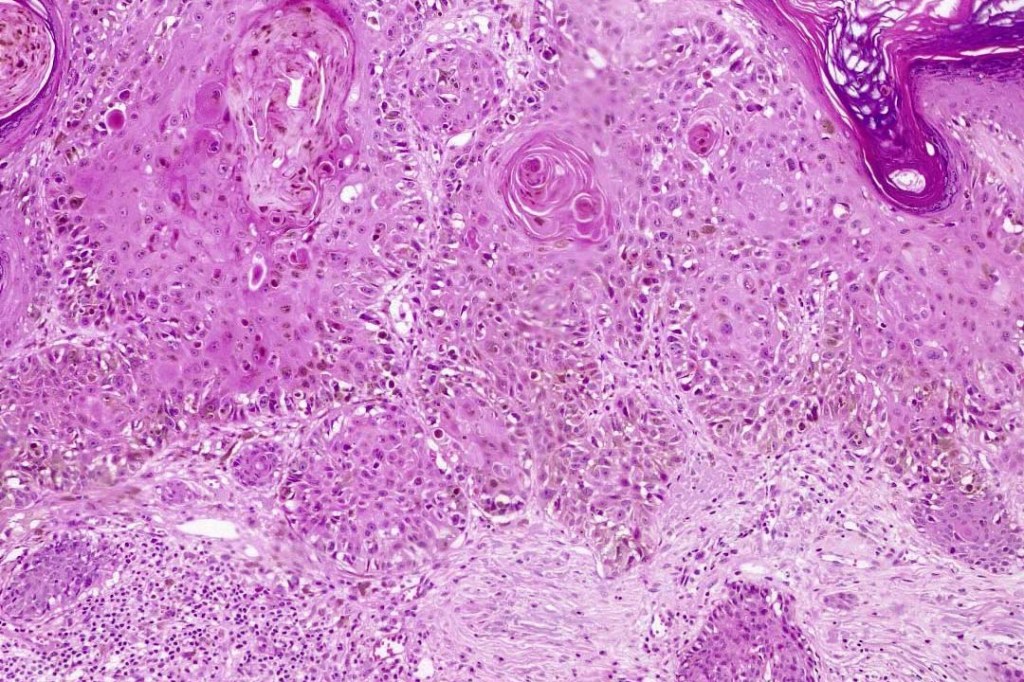

An exceedingly rare collision tumor composed of an admixture of squamous cell carcinoma/basal cell carcinoma/trichoblastoma respectively and melanoma. Although most appear to have behaved in a benign fashion, a malignant basomelanocytic tumor is illustrated below. More cases will be need to be stidies/published before the true biological behavior of this group of tumors can be satisfactorily elucidated. I think that complete excision should be the rule and a careful follow-up recomended.

Basomelanocytic tumor

Squamomelanocytic tumor